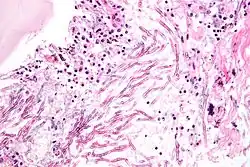

Aspergillosis. H&E stain.

The most common pathogenic species are Aspergillus fumigatus and Aspergillus flavus. Aspergillus flavus produces aflatoxin which is both a toxin and a carcinogen and which can potentially contaminate foods such as nuts. Aspergillus fumigatus and Aspergillus clavatus can cause allergic disease. Some Aspergillus species cause disease on grain crops, especially maize, and synthesize mycotoxins including aflatoxin. Aspergillosis is the group of diseases caused by Aspergillus. The symptoms include fever, cough, chest pain or breathlessness. Usually, only patients with weakened immune systems or with other lung conditions are susceptible.[1]

The spores of Aspergillus fumigatus are ubiquitous in the atmosphere. A. fumigatus is an opportunistic pathogen. It can cause potentially lethal invasive infection in immunocompromised individuals.[10] A. fumigatus has a fully functional sexual cycle that produces cleistothecia and ascospores.